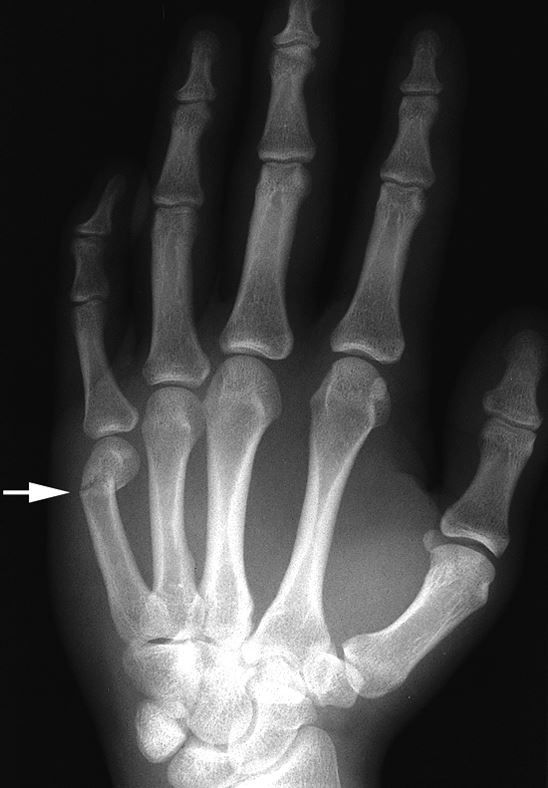

De diagnose van een boxerbreuk gebeurt meestal door middel van een lichamelijk onderzoek en röntgenfoto's. De arts zal de hand onderzoeken op zwelling, pijn en bewegingsbeperking. Röntgenfoto's helpen om de locatie en de ernst van de breuk te bepalen. Soms is een CT-scan nodig voor een gedetailleerder beeld.